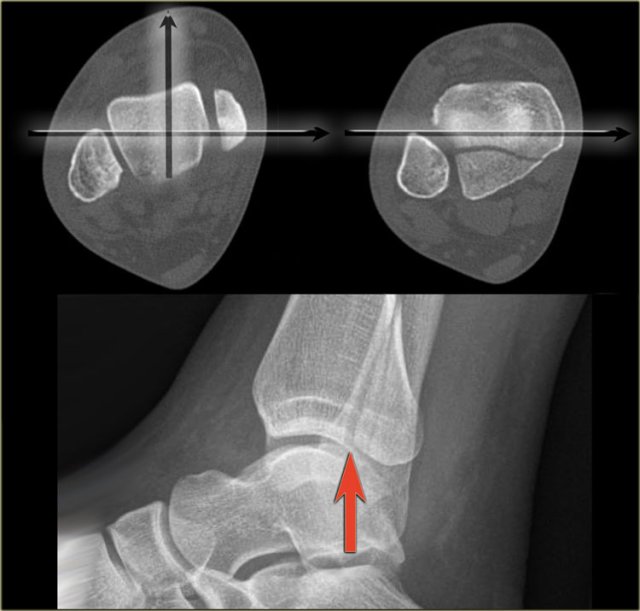

Malpositioning of the lateral view is the most common mistake in radiography of the injured ankle.

Because the patient is in pain, the technologist is afraid to let the patient turn the ankle fully lateral.

This is one of the reasons why we miss so many fractures of the posterior malleolus.

The CT demonstrates a large tertius fracture.

On the lateral view and also on the AP- and Mortise views, which will be shown in the paragraph on tertius fractures, this fracture was not visible.

The explanation is that on the lateral radiograph the fibula projects in the middle of the tibia.

The x-ray beam is not parallel to the fracture line.

Since the fracture line of a tertius fracture always has this orientation, we must insist on a true lateral view.